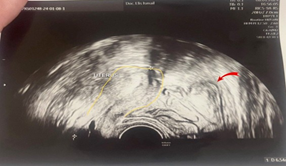

A 23-year-old asymptomatic female patient. During a routine gynecological examination, pelvic ultrasound identified a nonspecific tumor-like mass of solid consistency (Figures 1-3). The patient is sexually active and nulliparous. She has no history of abnormal menstrual bleeding or pelvic pain. Pelvic ultrasonography demonstrated a nonspecific tumor-like mass. The lesion was located in the vesicouterine space, anterior to the uterus (which was in anteversion and anteflexion with length 6.5 cm.) and posterior to the urinary bladder. The mass measured approximately 10 cm and had a predominantly solid component, with multilaminar hypoechoic bands within its capsule (Figures 1 and 4). Both ovaries were visualized and appeared normal on transvaginal ultrasonography (Figures 2 and 3). The pouch of Douglas is free of fluid.

Figure 4: Ultrasonographic image showing the uterus (outline in yellow) and an adjacent hydatid cyst (indicated by a red arrow).